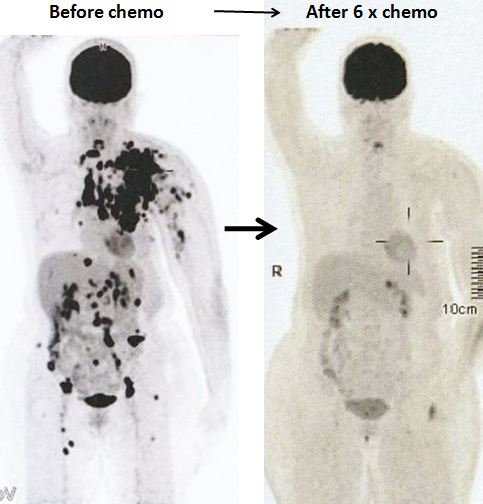

8. Pemindaian PET pada 14 April 2022 memang menunjukkan respon yang baik.

Sebelum kemo ———– setelah 6 siklus kemo

1. Temuan scan menunjukkan respon metabolik lengkap pada kekambuhan dinding dada, metastasis nodal dan penyebaran jauh.

2. Perubahan atelektasis baru pada dasar paru kiri dengan efusi pleura kiri ringan mungkin disebabkan oleh infeksi baru-baru ini.

Bandingkan ketiga gambar ini :

Kiri: Setelah operasi Lucy menjalani terapi alternatif, menolak kemoterapi. Hasilnya adalah metastasis luas (tengah).

Kanan: Lucy tidak punya pilihan selain menjalani kemoterapi. Hasil dari 6 siklus kemoterapi sungguh luar biasa! Selama lebih dari 25 tahun saya berurusan dengan pasien kanker, saya belum pernah melihat hasil kemoterapi yang luar biasa seperti ini. Salut dengan ahli onkologi! Anda menyelamatkan Lucy!

Faktanya, hasil chemo ini sangat sulit dipercaya sehingga orang tergoda untuk bertanya apakah itu asli dan bukan palsu? Jawaban saya TIDAK, studi detail hasil PET scan di bawah ini adalah nyata! Kaji gambar berikut dengan cermat – sebelum dan sesudah kemoterapi.